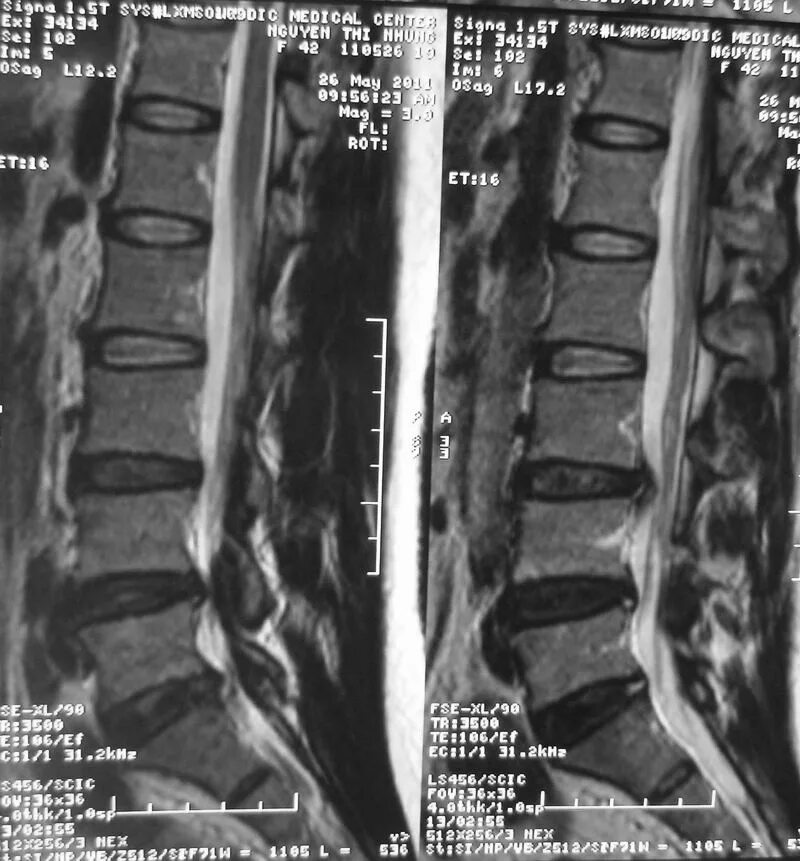

Спондилоартроз на уровне l1 s1